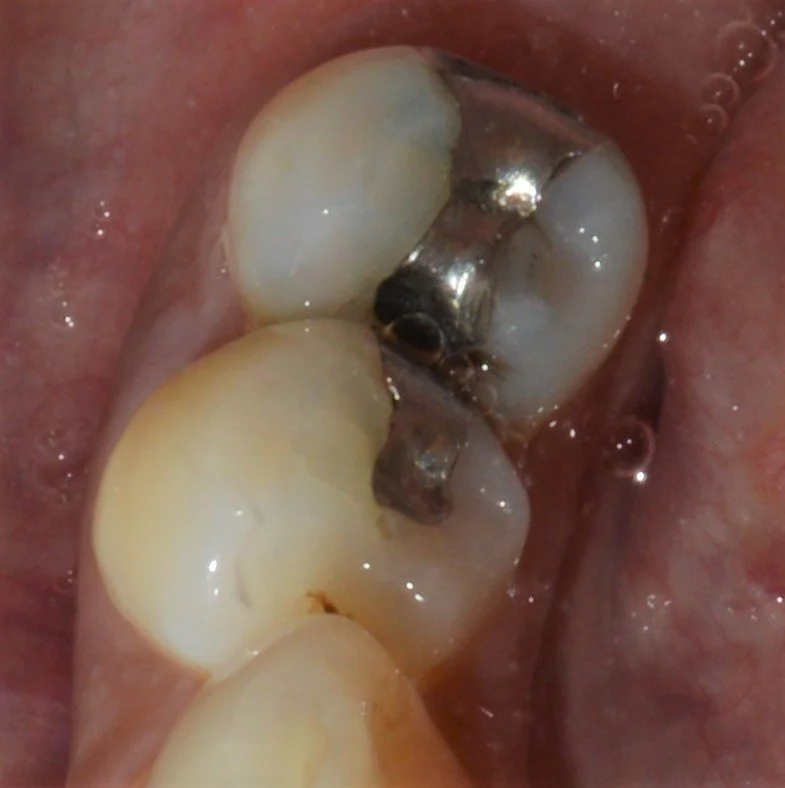

补牙是一项牙齿治疗方法,主要把你牙齿上蛀牙的地方清洁干净,然后补上白色树胶的补牙材料或者银汞材料。我们诊所大多数情况下都会提供白色树胶补牙,银汞在特定的情况下才会使用。

银汞补牙